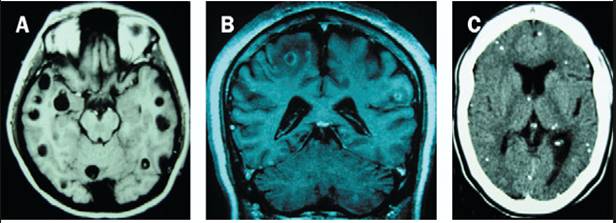

Có hai cách nhiễm trùng có thể thiết lập dựa trên con đường gây nhiễm. Bước đầu tiên là do nuốt trứng do các động vật và người nhiễm đào thải qua phân, dẫn đến phát triển thành ấu trùng (larval stage) bên trong các mô của động vật và người, gọi là bệnh ATSDL. Nếu các ấu trùng phát triển trong hệ thần kinh trung ương, gọi là ATSDL thần kinh (neurocysticercosis_NCC).

Loại thứ hai là bản thân nuốt phải các ấu trùng từ các nguồn thịt nấu không chín, dẫn đến phát triển và nhiễm trùng sán dây trưởng thành trong đường tiêu hóa. Các nhiễm trùng sán dây nói trên có ý nghĩa về mặt y học con người và y học thú y cũng như tác động trên kinh tế. NCC là một trong những nguyên nhân quan trọng dẫn đến động kinh và chiếm 30% số ca động kinh tại các quốc gia đang phát triển.

Theo dữ liệu từ Tổ chức Y tế thế giới ngày 15.02.2018 cho biết các khía cạnh chính của bệnh sán dây/ ấu trùng sán dây lợn (Taeniasis/cysticercosis) cần quan tâm:·Bệnh sán dây là một nhiễm trùng đường ruột do nhiễm sán dây trưởng thành; ·Ba loài sán dây gây bệnh sán dây ở người đến nay được biết là Taenia solium, Taenia saginata và Taenia asiatica. Chỉ có T. solium mới gây vấn đề sức khỏe công cộng nghiêm trọng; Bệnh sán dây lợn T. solium mắc phải ở người do tiêu hóa phải nang ấu trùng sán dây (cysticerci) trong các mẫu thịt nhiễm và nấu chưa chín; ·Người mang sán dây sẽ đào thải trứng sán dây ra theo phân và nhiễm vào trong môi trường nếu không đi vào hố xí; ·Người cũng có thể nhiễm trứng sán dây lợn T. solium do ăn các thức ăn hoặc uống nguồn nước bị nhiễm hay nguồn ô nhiễm, không hợp vệ sinh; ·Tiêu hóa phải trứng sán dây T. solium, trứng phát triển thành ấu trùng (gọi là cysticerci) trong nhiều cơ quan khác nhau của cơ thể. Khi chúng vào hệ thần kinh trung ương (TKTU), có thể gây ra các triệu chứng thần kinh gọi là bệnh ấu trùng sán dây thể thần kinh (ATSDTK-neurocysticercosis), gồm cả động kinh, co giật; ·T. solium là tác nhân gây ra 30% số ca động kinh tại nhiều vùng lưu hành, nơi mà con người và lợn thả rông (roaming pigs) sống gần nhau; ·Hơn 80% trong số 50 triệu người bị nhiễm có biểu hiện động kinh sống tại các quốc gia có thu nhập thấp và trung bình thấp. Bệnh sán dây bao gồm 2 loại là sán dây lợn và sán dây bò, thuộc nhóm C trong Luật Phòng, chống bệnh truyền nhiễm. Bệnh sán dây có thể ký sinh ở người dưới hình thức sán trưởng thành và ấu trùng sán dây lợn.   |